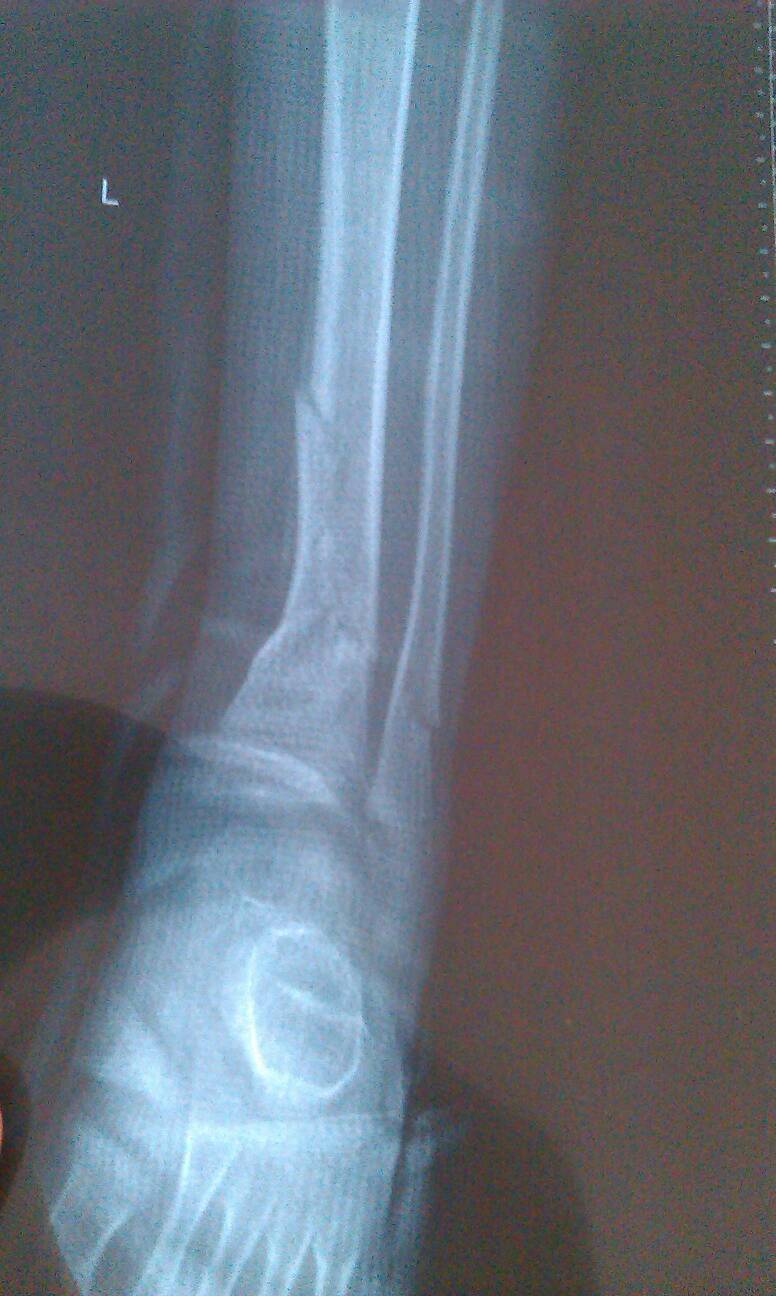

5岁孩子左胫腓骨骨折,手法复位后石膏固定20天,刚拍的X线片子,不懂,不知道现在该怎么办,对以后行 5岁孩子左胫腓骨骨折,手法复位后石膏固定20天,刚拍的X线片子,不懂,不知道现在该怎么办,对以后行走有没有影响,请专家给予中肯的指导意见,谢谢!(附X线照片) 点击展开 匿名用户 2015-04-22 15:50 满意回答 恢复的很好 对以后 没有任何影响 放心吧 匿名用户 2015-04-22 22:17 宝宝知道提示您:回答为网友贡献,仅供参考。 相关问题 一岁半的宝宝左胫腓骨远端骨折打石膏后晚上老是哭闹怎么办? 宝宝今年2周岁半,被电动车倒了砸到脚了,拍片子说右足第1跖骨骨折,断端错位了,现在上了石膏,后期应 小孩骨折打石膏期间给碰撞了下,有一会痛感,要去拍片子吗?一